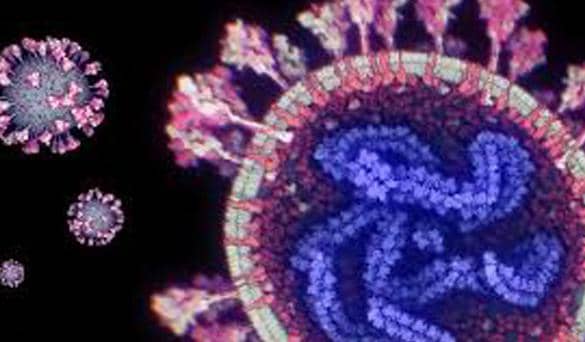

اكتشاف فيروس كورونا جديد في خفافيش البرازيل يثير مخاوف انتقاله للبشر

كشف علماء من الولايات المتحدة واليابان عن اكتشاف فيروس كورونا جديد في خفافيش البرازيل، يشترك في عدة خصائص رئيسية مع الفيروس المسبب لجائحة كوفيد-19، ما أثار مخاوف من احتمال ظهوره كفيروس قادر على إصابة البشر. وأُطلق على الفيروس اسم BRZ batCoV، وتم اكتشافه بعد اصطياد... لـ دلتا برس | 31/10/2025